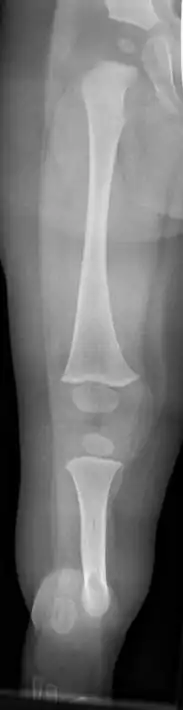

X-ray image of fibular hemimelia type II (fibula completely absent)

Fibula hemimelia in patient affecting right side